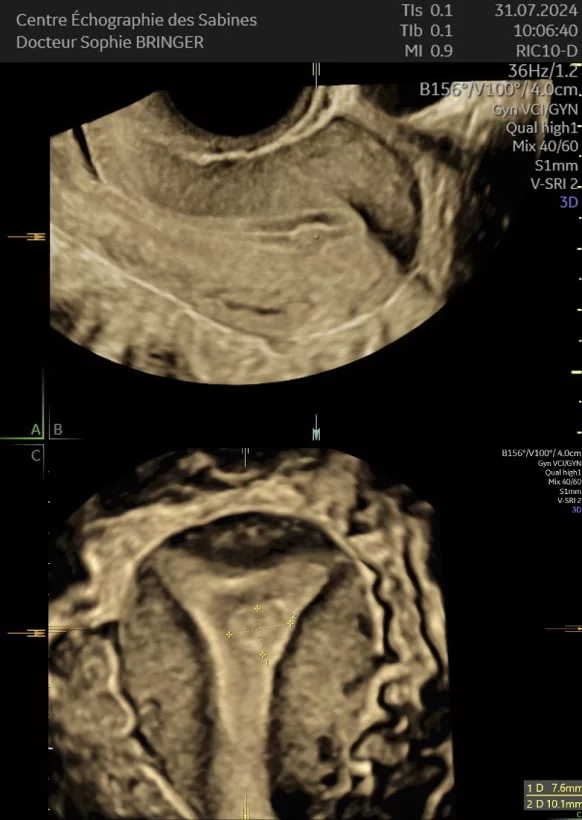

L’Échographie par voie endo-vaginale

Nécessite votre consentement explicite et absolu avant de pouvoir être pratiqué.

L’examen ne doit pas être douloureux.

Sera réalisé dans le respect de l’intégrité physique et morale de la patiente.

Signaler au praticien tous facteurs ou toutes raisons pouvant rendre l’examen désagréable.

L’examen pourra être interrompu à votre demande et sans que vous n’ayez besoin de vous justifier à n’importe quel moment.

Si vous n’avez jamais eu de rapport sexuel, l’examen sera réalisé par voie abdominale.